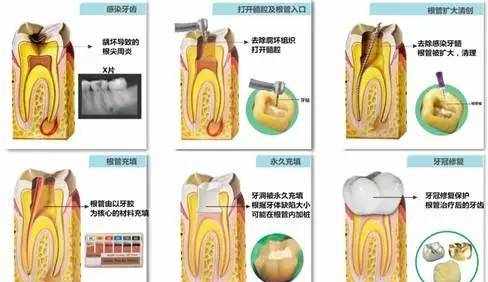

根管治疗的过程:(见图)

根管预备--去除牙齿腐坏组织,打开牙髓腔,用一套金属锉将根管扩大并用消毒药水将其中的感染碎屑冲洗出来。

根管充填--使用根管充填材料将清理干净后的根管系统封闭起来。

根管消毒封药--如果根管里有感染残留,医生可能会在根管内封抗菌药,下次就诊时根据感染是否得到控制,决定是否做根管充填。

根管治疗的过程:(见图)

根管预备--去除牙齿腐坏组织,打开牙髓腔,用一套金属锉将根管扩大并用消毒药水将其中的感染碎屑冲洗出来。

根管充填--使用根管充填材料将清理干净后的根管系统封闭起来。

根管消毒封药--如果根管里有感染残留,医生可能会在根管内封抗菌药,下次就诊时根据感染是否得到控制,决定是否做根管充填。